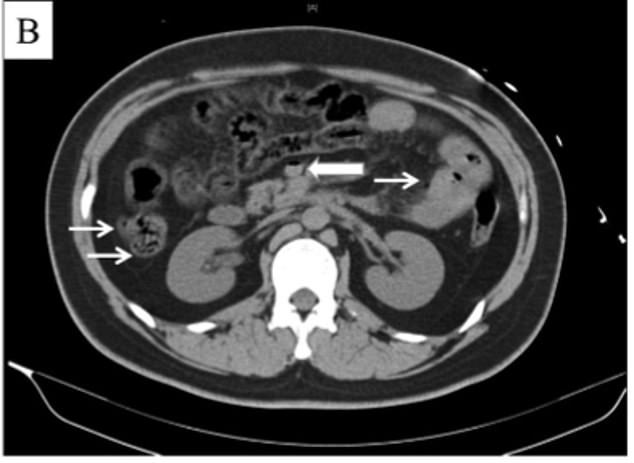

ภาพถ่ายซีทีสแกนของหนุ่มจีนที่ไม่ได้รับการเปิดเผยชื่อ ถูกนำตัวส่งโรงพยาบาลจ้าวหยาง ในกรุงปักกิ่ง หลังมีอาการปวดท้องรุนแรง และท้องบวม เขาบอกกับแพทย์ว่า เมื่อ 6 ชั่วโมงก่อน เขาดื่มน้ำอัดลม "Coca Cola" ขนาด 1.5 ลิตร หมดใน 10 นาที เพื่อบรรเทาความกระหาย เนื่องจากอากาศร้อน

ซึ่งแพทย์วินิจฉัยว่า การดื่มน้ำอัดลมในปริมาณที่มากและรวดเร็วขนาดนั้น ทำให้เกิดการสะสมของแก๊สในลำไส้ และรั่วเข้าไปในหลอดเลือดดำพอร์ทัล ซึ่งเป็นหนึ่งในหลอดเลือดหลักที่ไปเลี้ยงตับ และไปยังส่วนอื่นๆ ของร่างกายอีกด้วย